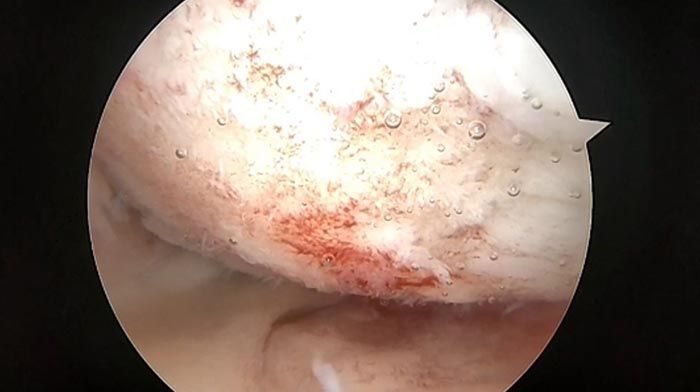

ARTROUPN - Artroscopía de hombro

ButtonARTROUPN - Preservación de cartilago